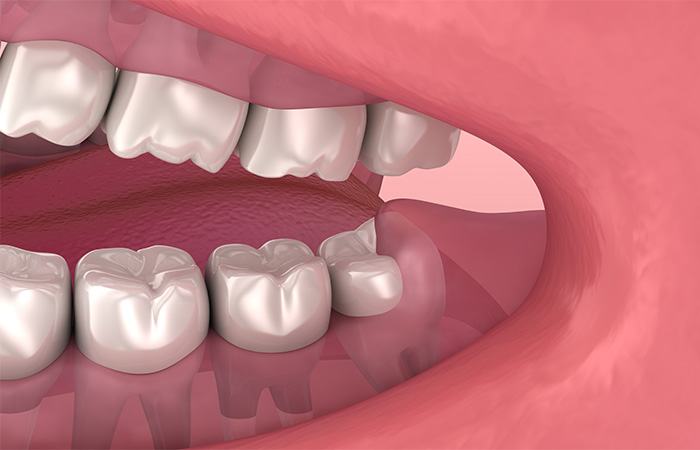

半分歯ぐきに埋まっている

歯磨きが行き届かず、むし歯や歯周病などのトラブルが起こる場合は、抜歯が勧められます。